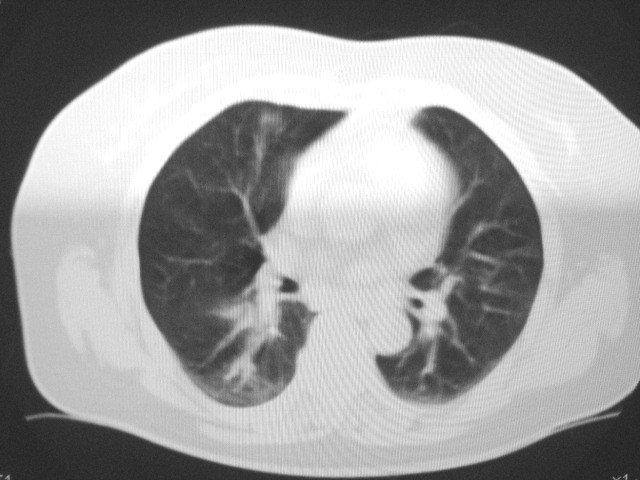

以下是引用清清楚楚在2007-8-28 7:13:00的发言:[br]右肺下叶可见斑片状高密度影,边缘模糊;右肺中叶内侧段及左肺舌段亦可见小斑片状模糊影。[br]考虑双肺感染,建议抗炎治疗后复查。

以下是引用天南地北在2007-8-27 23:49:00的发言:[br]右肺下叶可见斑片状高密度影,边缘模糊;右肺中叶内侧段及左肺舌段亦可见小斑片状模糊影。[br]考虑双肺感染,建议积极抗炎治疗后复查。

以下是引用天南地北在2007-8-27 23:49:00的发言:[br]右肺下叶可见斑片状高密度影,边缘模糊;右肺中叶内侧段及左肺舌段亦可见小斑片状模糊影。[br]考虑双肺感染,建议抗炎治疗后复查。

以下是引用难听在2007-8-28 13:17:00的发言:[br]右肺下叶背段支气管狭窄,是否可以考虑新生物伴阻塞性肺炎.请大家帮帮忙,这个病人是卫生局长的丈母娘.惹不起啊.